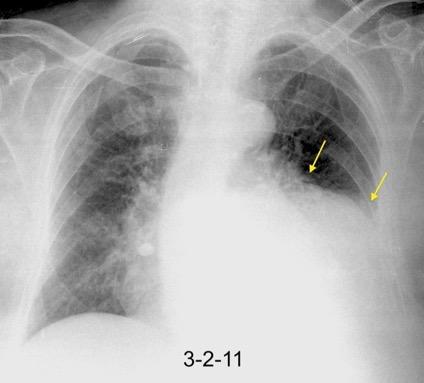

Nefrectomia derecha en 1996 por adenocarcinoma renal. Reseccion de metastasis pulmonar en LSI de carcinoma renal. Sospecha de nueva metástasis.

Granuloma de cuerpo extrano por hilo de sutura en situación cisural